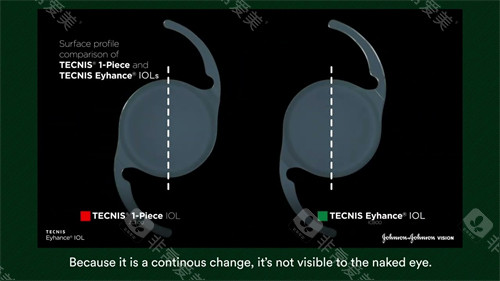

无衍射环设计:

传统多焦点晶体依赖衍射环分割光线,易产生光晕干扰;艾无极采用高阶渐进折射技术,光学区度数从周边向中央平滑递增,形成连续焦深,实现33厘米至无限远的平滑过渡。